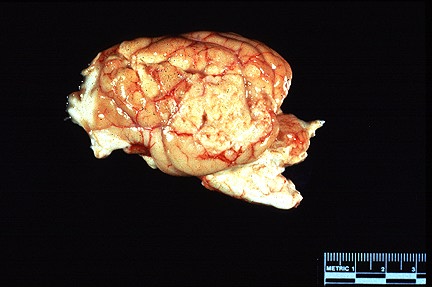

3.0 X 4.0 granular whitish-tan neoplasm on the left temporal lobe in a Springer Spaniel. (29K)

Sagittal section through the skull of a Springer Spaniel showing a white-tan mass adherent to the meninges. (86K)

Gross Pathology: The animal had 3.0 x 4.0 cm white-tan, granular focus on the lateral aspect of the temporal lobe of the left cerebral hemisphere. This area and the meninges were adhered to the parietal and temporal bones. On cross-section, the mass compressed and invaded the cerebrum.

AFIP Diagnosis: Cerebrum, meninges: Granular cell tumor, Springer Spaniel, canine.